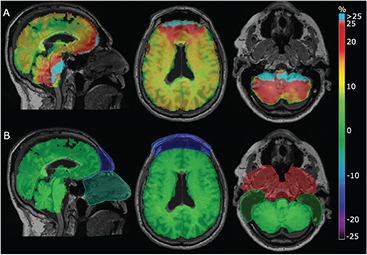

The attenuation maps obtained with our method in comparison with the vendor provided UTE and the gold standard CT image are shown in figure 5. Dixon was excluded from this analysis, as the MR-AC map does not contain any bone. The Dice coefficients for the overlapping bone were 0.71 for UTE and 0.81 for RESOLUTE. The averaged %-difference to the LAC in bone voxels in the aligned CT was −16% ± 6% (max: −36%) when using UTEs fixed LAC value for bone. This was reduced to −1% ± 3% (max: −8%) when using RESOLUTE with continuous bone value, suggesting that the  map is indeed able to measure the correct bone density.

Figure 5. Comparison of attenuation maps for a representative subject. MR-ACUTE (A), MR-ACRESOLUTE (B), and MR-ACCT (C) are displayed in 3 orientations (the neck area not covered by the CT has been replaced by the corresponding Dixon voxels in all images). Notice the air segmentation in the nasal septa (blue arrows) and air/bone segmentation in the frontal sinus (red arrows).

In this study we have presented our new attenuation correction method (RESOLUTE) for brain PET/MR hybrid imaging. The only MR sequence used is UTE, and from this we measure the bone density of each patient, and classify voxels as brain, CSF, air and soft tissue using segmentation techniques. Challenging areas of the nasal septa, ethmoidal-, frontal sinuses and mastoid process in the skull base are handled separately using regional masks. The errors in the reconstructed PET data based on our method are small; from a comprehensive quantitative analysis we highlight that the average error in the brain is 0.1%, less than 1.2% in all regions of the brain and on average 95% of the brain voxels are within ±10% of the PET value derived using CT-based AC. The process to create the attenuation map takes 10–15 min on a standard desktop computer, and is fully automatic.

The produced attenuation map looks very similar to that of CT (figure 5), and is a clear improvement over the vendor-provided UTE technique, both with respect to bone density, thickness, and accuracy of bone and air, especially in the frontal sinus area. The average LAC %-difference to CT in bony voxels was 1%, and maximum 8%, suggesting that the  signal is indeed able to measure the patient specific bone density.